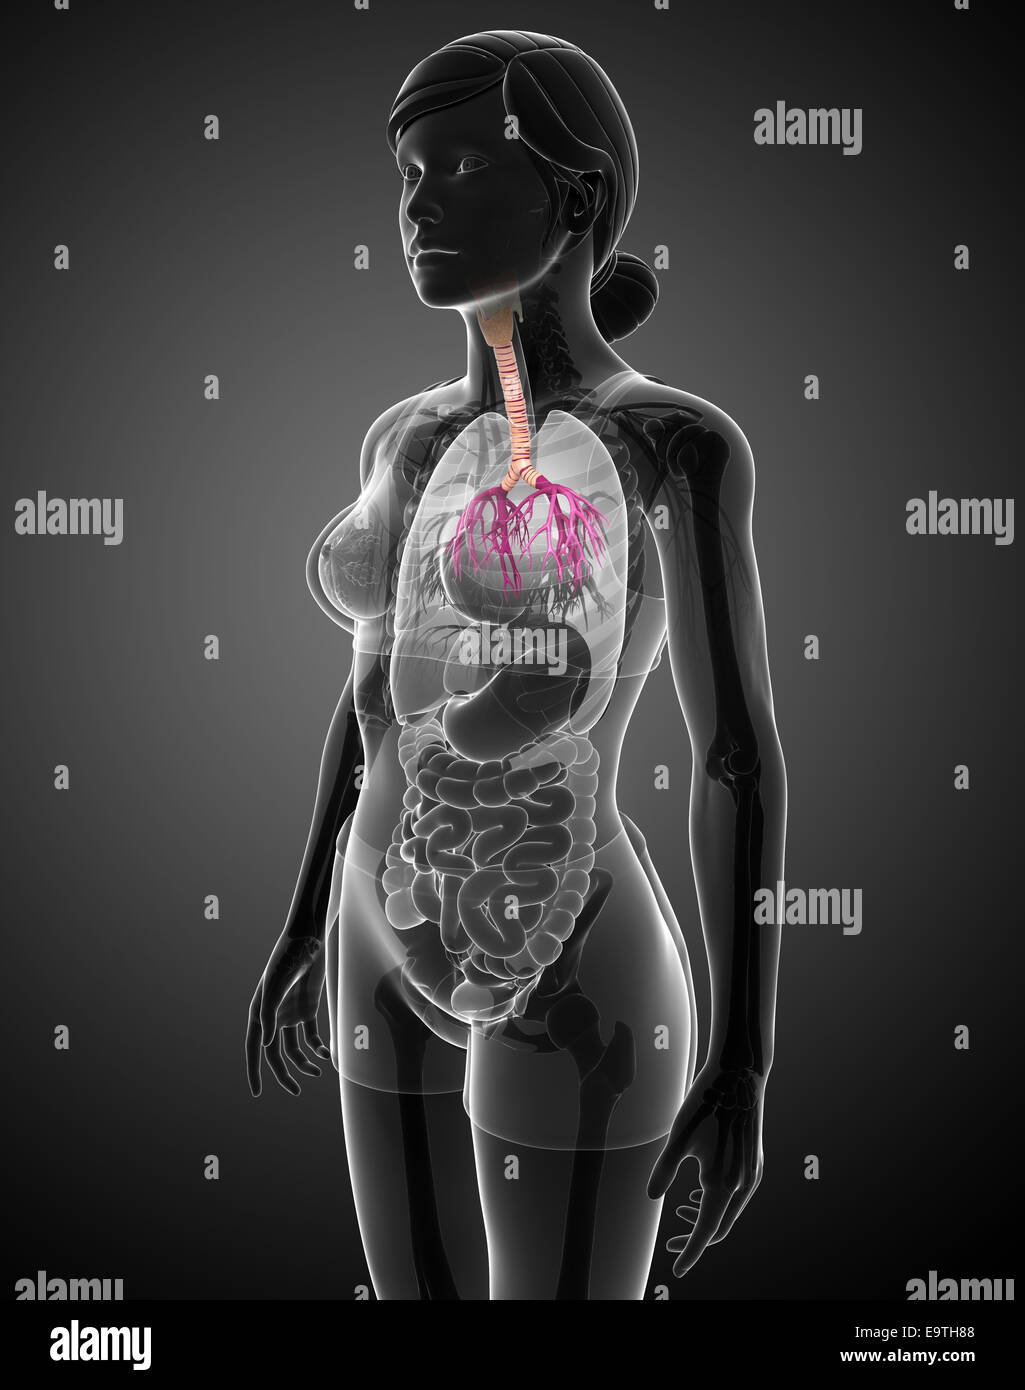

Illustration de l'anatomie de la gorge femelle Banque D'Imageshttps://www.alamyimages.fr/image-license-details/?v=1https://www.alamyimages.fr/photo-image-illustration-de-l-anatomie-de-la-gorge-femelle-74913784.html

Illustration de l'anatomie de la gorge femelle Banque D'Imageshttps://www.alamyimages.fr/image-license-details/?v=1https://www.alamyimages.fr/photo-image-illustration-de-l-anatomie-de-la-gorge-femelle-74913784.htmlRFE9TH88–Illustration de l'anatomie de la gorge femelle